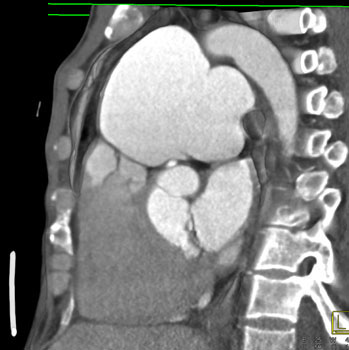

![]() | Question 12: 59 year old male with recent onset of chest pain as well as shortness of breath. The patient had a history of “some type of corrective cardiac surgery” as a child. What is the diagnosis? |